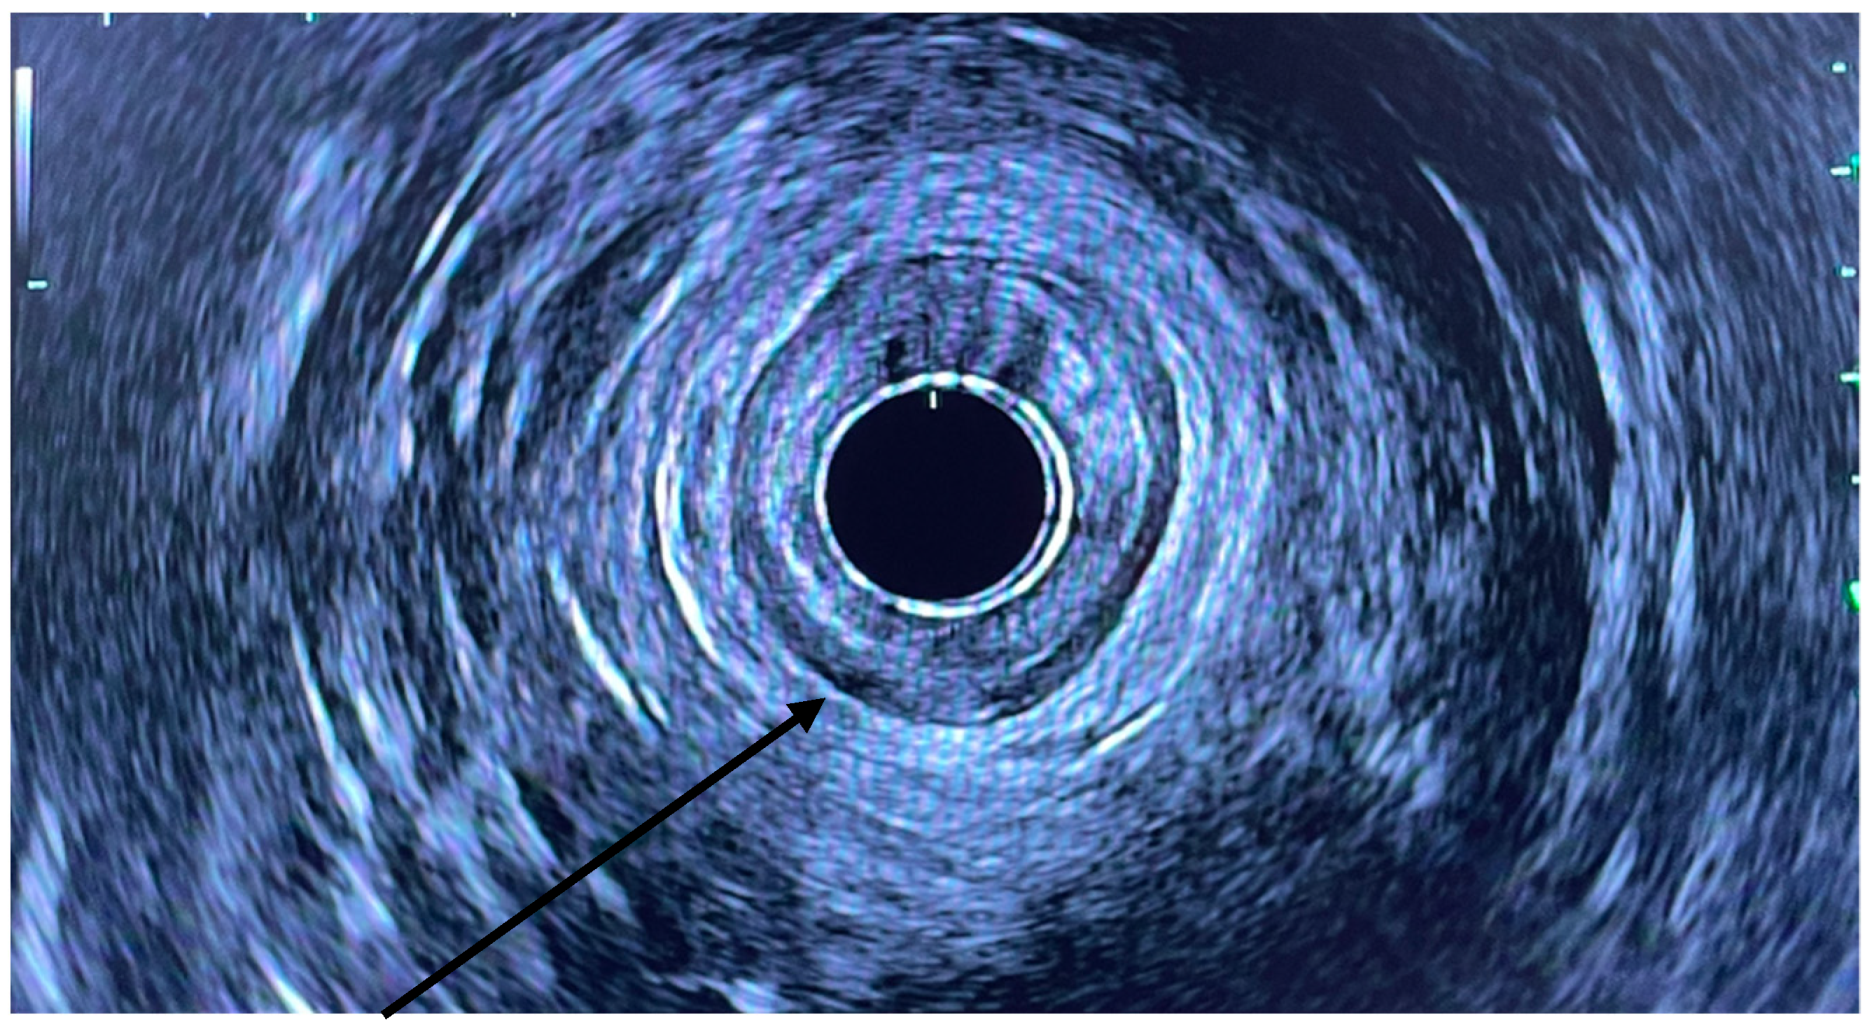

EUS was performed using a linear array echoendoscope (Figure 1, Figure 2 and Figure 3). Eighty units of type A botulinum neurotoxin was diluted in 2 cc of isotonic saline. An echoendoscope was introduced into the anal canal. The internal sphincter was identified sonographically and a 25-gauge needle was introduced into the internal sphincter. Then, 0.5 cc of saline-containing 20IU BTX was injected into the internal sphincter. The needle was withdrawn, the scope was rotated 90 degrees and the second injection was given. This process was repeated for a total of 4 times giving 0.5 cc per quadrant. Conscious sedation or MAC anesthesia was used for the procedure.

Figure 1. Radial EUS with arrow pointing to IAS.